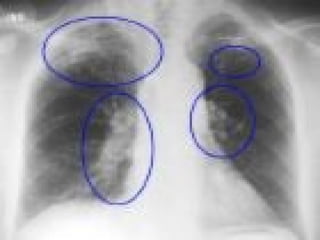

Diagnostico radiologico EXPOSICION PASADA Placas pleurales  Engrosamiento o calcificación a lo largo de la pleura parietal Principalmente en campos pulmonares inferiores, diafragma y borde cardiaco Dx. Radiológico de asbestosis Opacidades irregulares o lineales en campos pulmonares inferiores y se va extendiendo a los medios y superiores a medida que avanza la enfermedad A veces el pulmón presenta aspecto de “vidrio esmerilado”

Diagnostico radiologico EXPOSICIONPASADA Placas pleurales Engrosamiento o calcificación a lo largo de la pleura parietal Principalmente en campos pulmonares inferiores, diafragma y borde cardiaco Dx. Radiológico de asbestosis Opacidades irregulares o lineales en campos pulmonares inferiores y se va extendiendo a los medios y superiores a medida que avanza la enfermedad A veces el pulmón presenta aspecto de “vidrio esmerilado”